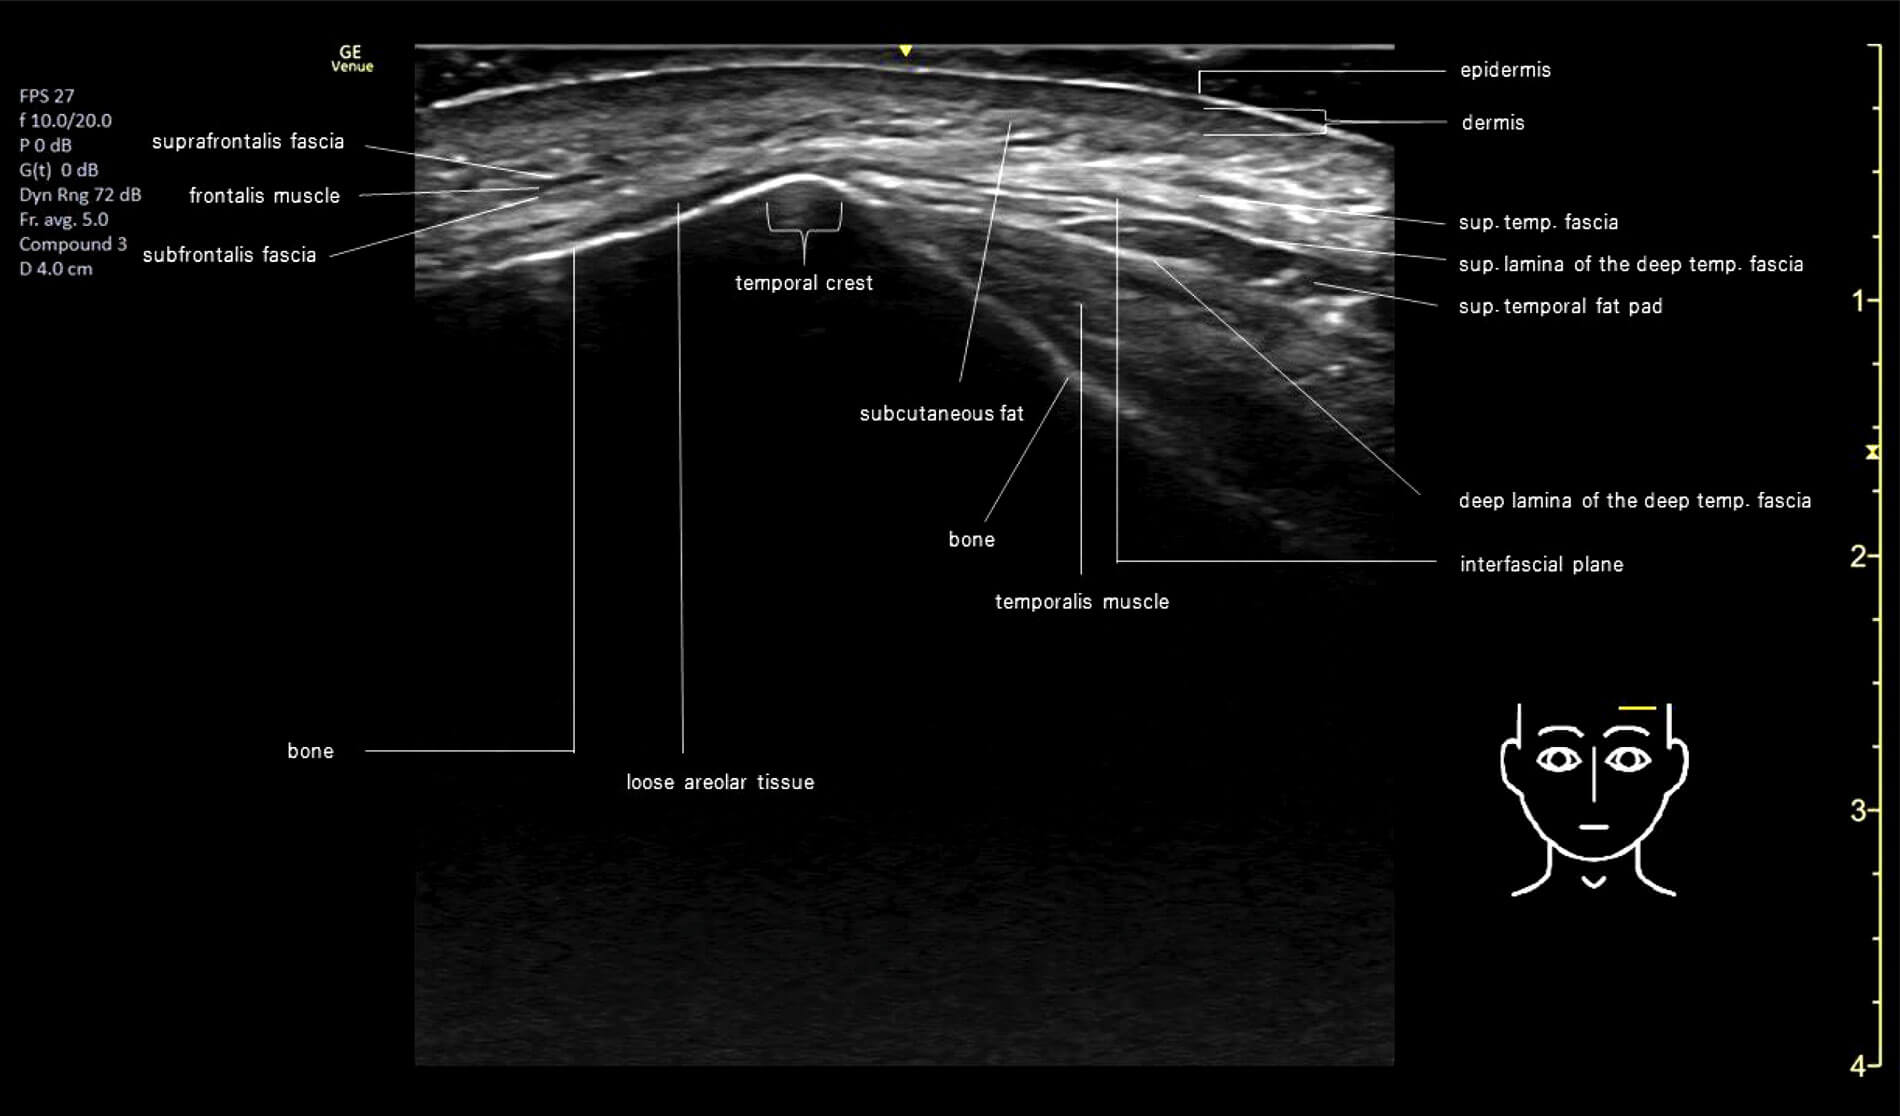

Enhancing safety in upper face injections: Anatomical considerations for precision and efficacy

The upper face, including forehead and temples, is often overlooked in non-surgical cosmetic procedures with dermal fillers. While horizontal forehead or glabella lines may be a common complaint amongst patients, seldom do they attend with concerns of loss of volume...